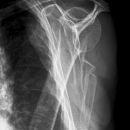

Dislozierte subcapitale Fraktur mit Tbc majus